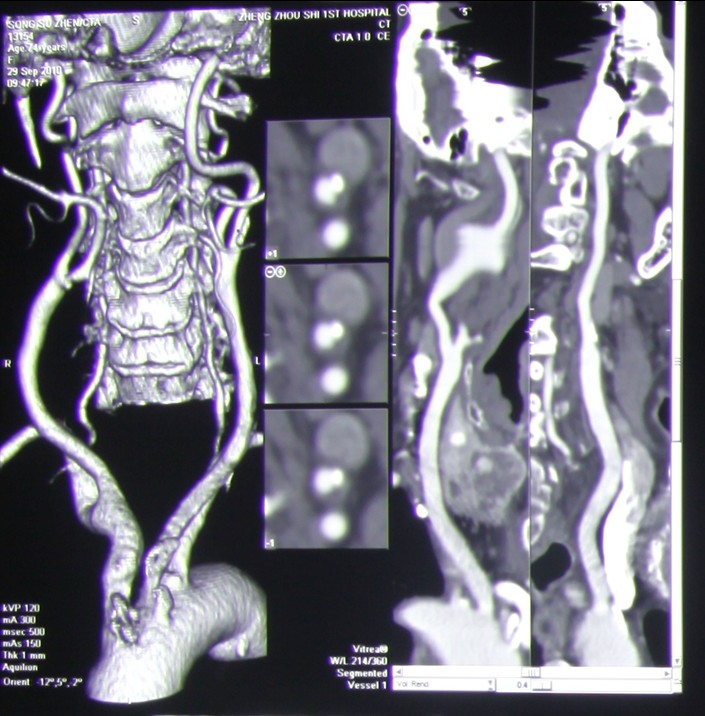

辅助检查:1.头颅CTA:

2.    颈部CTA: